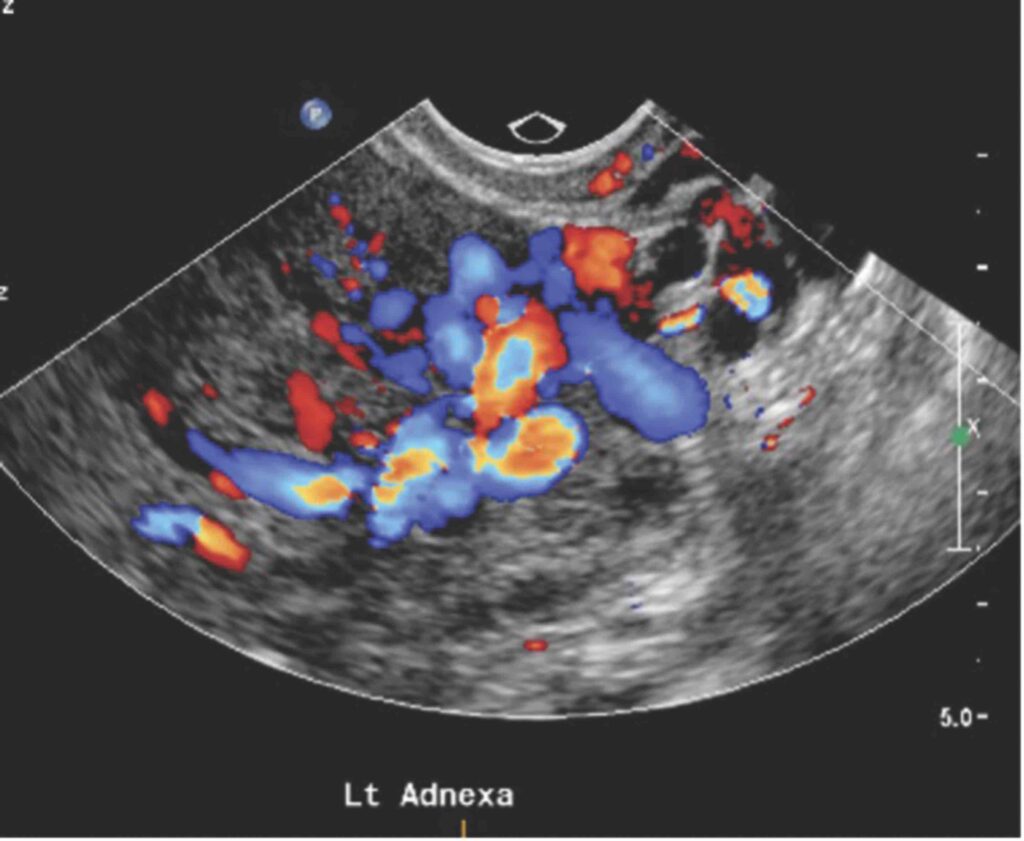

Ультразвуковое исследование - первый и главный шаг

«Золотым стандартом» неинвазивной диагностики является ультразвуковое исследование, выполненное на аппарате экспертного класса. Врач проводит его в несколько этапов: трансабдоминально (датчиком по животу) и трансвагинально. Это позволяет не просто осмотреть матку и яичники, но и прицельно изучить сосудистые сплетения вокруг них. С помощью специального допплеровского режима врач может:

- Обнаружить варикозно расширенные вены и измерить их диаметр (диагностически значимым считается диаметр более 5 мм).

- Оценить скорость и, что самое главное, направление кровотока.

- Провести функциональные пробы (например, пробу Вальсальвы - натуживание), чтобы спровоцировать и зарегистрировать патологический рефлюкс (обратный заброс крови).

Именно выявление этого рефлюкса является ключевым подтверждением диагноза.